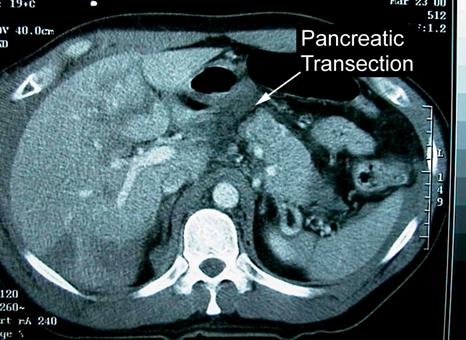

Traumatism abdominal inchis

Leziune de pancreas ( ambele foto)

Leziune pancreatica